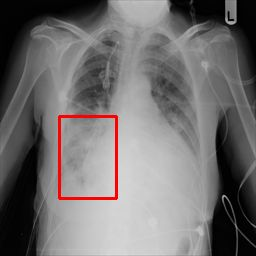

Deployments of artificial intelligence in medical diagnostics mandate not just accuracy and efficacy but also trust, emphasizing the need for explainability in machine decisions. The recent trend in automated medical image diagnostics leans towards the deployment of Transformer-based architectures, credited to their impressive capabilities. Since the self-attention feature of transformers contributes towards identifying crucial regions during the classification process, they enhance the trustability of the methods. However, the complex intricacies of these attention mechanisms may fall short of effectively pinpointing the regions of interest directly influencing AI decisions. Our research endeavors to innovate a unique attention block that underscores the correlation between 'regions' rather than 'pixels'. To address this challenge, we introduce an innovative system grounded in prototype learning, featuring an advanced self-attention mechanism that goes beyond conventional ad-hoc visual explanation techniques by offering comprehensible visual insights. A combined quantitative and qualitative methodological approach was used to demonstrate the effectiveness of the proposed method on the large-scale NIH chest X-ray dataset. Experimental results showed that our proposed method offers a promising direction for explainability, which can lead to the development of more trustable systems, which can facilitate easier and rapid adoption of such technology into routine clinics. The code is available at www.github.com/NUBagcilab/r2r_proto.